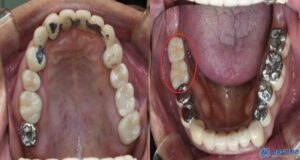

치료 마무리 후 사진입니다.

신흥동치과 신흥동치과

환자분께서는 임플란트 뿐만 아니라 신경치료 후

크라운 치료까지 진행하면서,

전체적인 구강 건강을 개선할 수 있었습니다.